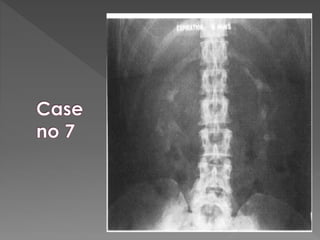

X ray films 1)Pre contrast 2) 5 mins 3) 25 mins 4) Post void